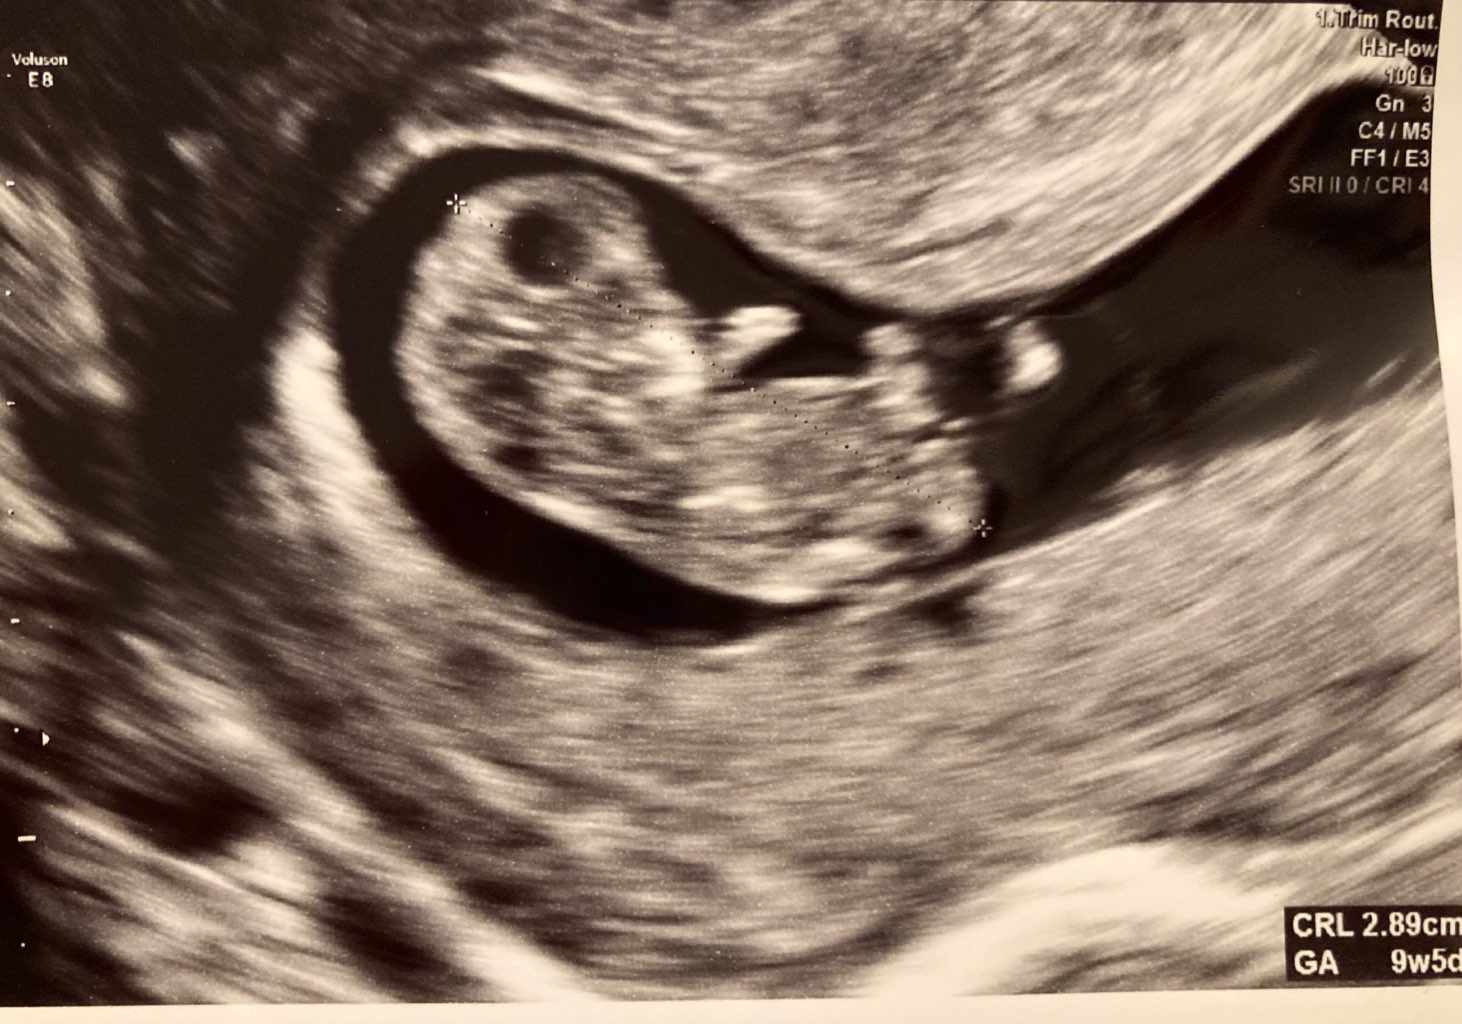

Bombelek:

Crl 22.80

Fhr 172

Termin porodu z USG przesuwa się o 5 dni wcześniej na 10.08

Mam jakieś drobne pole bezechowe przy sznurze pępowinowym, ale dr powiedział, że tym się nie przejmujemy.